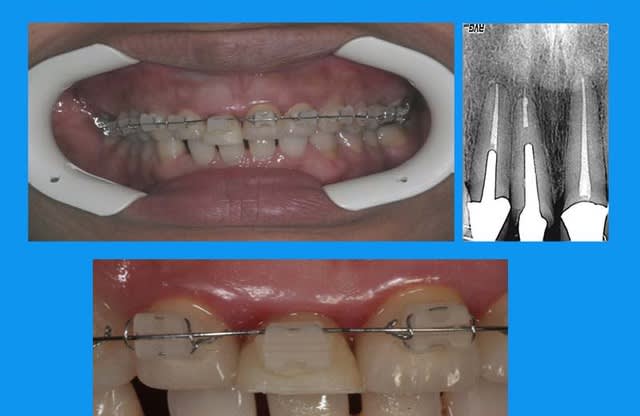

11 a du en passer par l'odf

curieux de voir que le dépassement a suivi la dent... serait un instrument cassé?

Dépassement dt5hca - Eugenol

traction en 3 mois

normalement la contention doit être laissée en place 3 mois minimum

cela dit ds ce cas,un ttt odf pr les incisives du bas ayant été entrepris,elle est restée plus longtemps

l'odf a utilisé un arc 0.014 thermique ,force constante faible

la dent provisoire a été meulée au fur et à mesure de la traction = 3mm